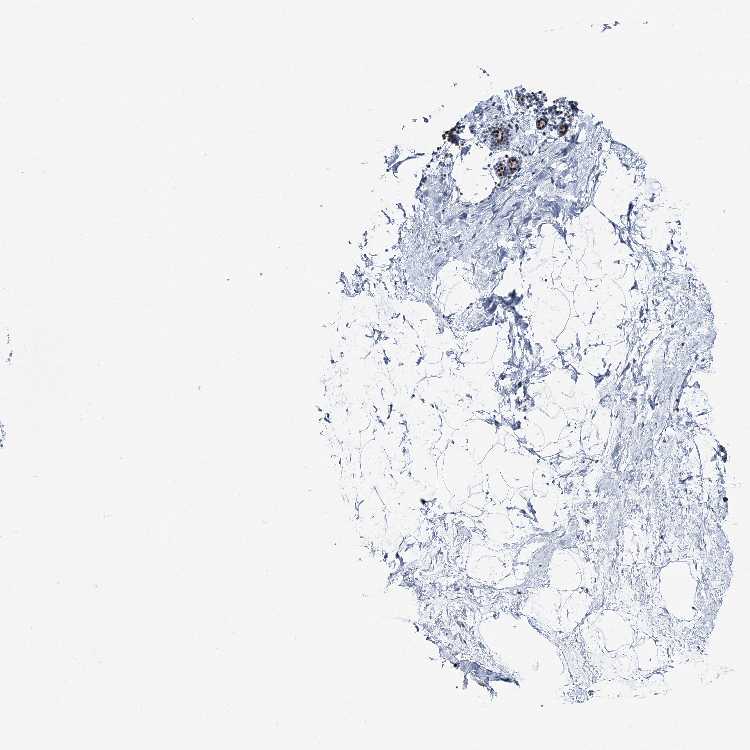

BREAST - Antibody stainingi

Antibody staining in the annotated cell types in the current human tissue is reported as not detected, low, medium, or high, based on conventional immunohistochemistry profiling in selected tissues. This score is based on the combination of the staining intensity and fraction of stained cells.

Each image is clickable and will lead to virtual microscopy that enables deeper exploration of all samples and also displays staining intensity scores, fraction scores and subcellular localization as well as patient and tissue information for each sample.

Antibody HPA036788Antibody CAB037191

Adipocytes Not detectedNot detected

Glandular cells LowMedium

Myoepithelial cells LowMedium